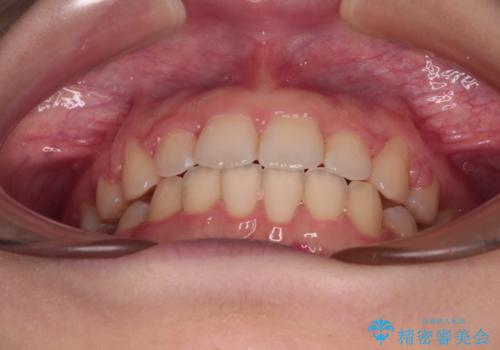

- 上下の前歯が突出しており、口が閉じにくいとのことで来院された患者様です。

上下前歯が著しく前突している状態であったので、上下左右の第1小臼歯4本を抜歯し、ワイヤー装置にて矯正治療を行うこととしました。